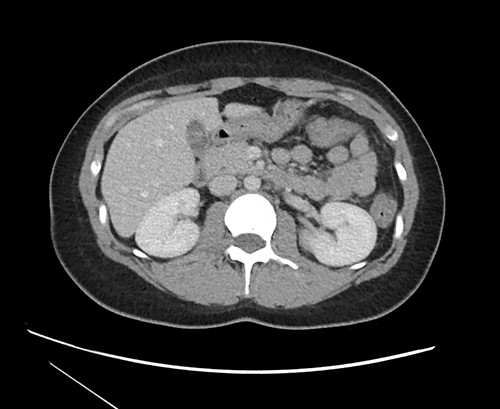

Multiseptate gallbladder is a rare congenital anomaly, with only 57 published articles in the literature [2]. This entity was first identified in 1963 [3]. It may be asymptomatic, however the majority will develop symptoms of biliary colic at some point [4]. The septations can be visualized by multiple imaging modalities including ultrasound, magnetic resonance cholangiopancreatography (MRCP) and endoscopic retrograde cholangiopancreatography (ERCP) [4]. In the case of our patient, the multiple septa could also be visualized on CT imaging, though it was not described initially by the interpreting radiologist (see Fig. 3).

CT imaging at time of presentation to the ED showing multiple septations within the gallbladder.